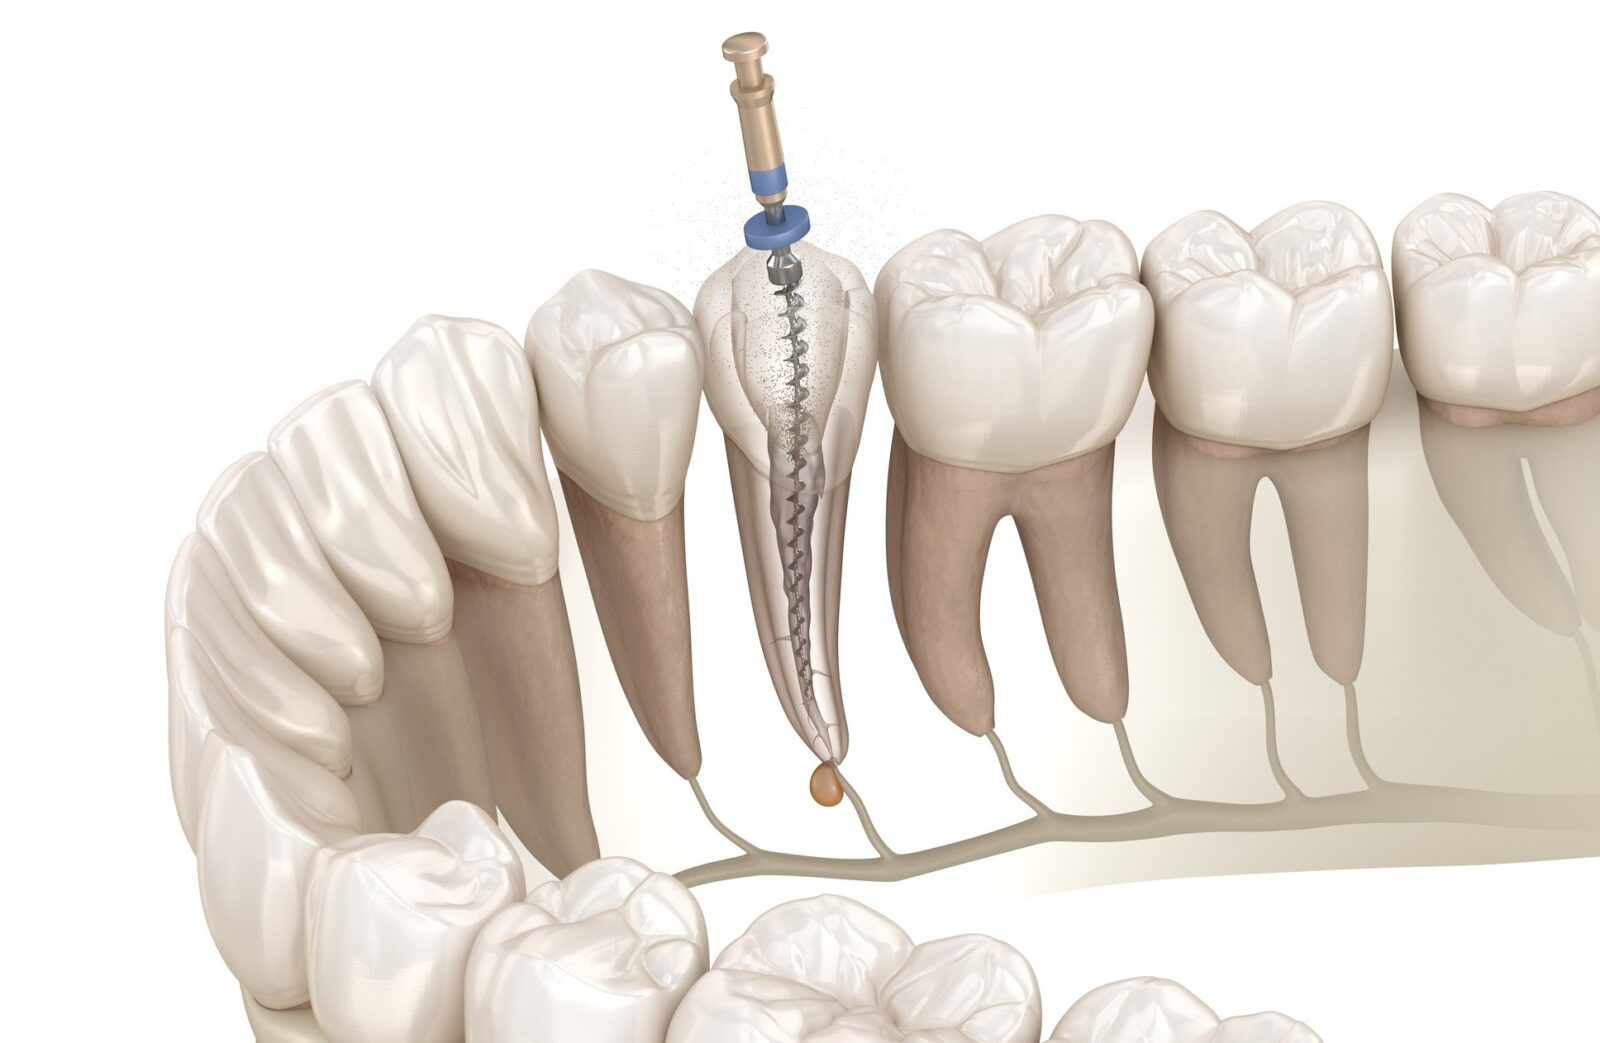

感染部位を除去する「ニッケルチタンファイル」

根管治療では、感染した神経や細菌を取り除くために、「ファイル」と呼ばれる細いヤスリ状の器具を使用します。多くの歯科医院では一般的にステンレス製のファイルが使われています。ステンレスは硬くしなりにくいため、曲がりくねった根管の形に合わせて動かすのが難しいという欠点があります。無理に操作すると、根の壁に傷をつけたり、最悪の場合は根に穴を開けてしまうリスクもあります。

当院では、このリスクを避けるために、高い柔軟性と弾力性を持つ「ニッケルチタン製ファイル」を使用しています。ニッケルチタンはしなやかに曲がる性質があり、どんなに複雑な根管形状にもスムーズに追従できるのが特徴です。この柔軟性によって、根の内部を傷つけることなく、感染部位だけを効率的かつ安全に除去することが可能になります。